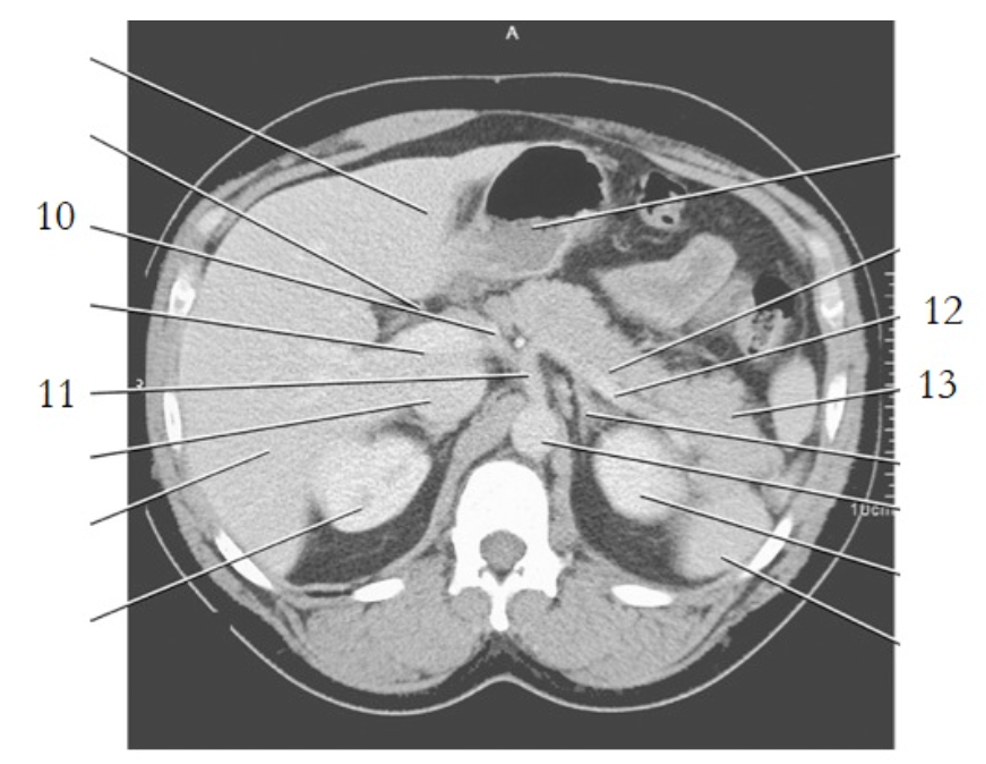

11

celiac axis

12

splenic artery

15

portal vein

20

aorta

24

19

left renal vein

1

liver

3

esophagus

stomach

spleen

9

crus of diaphragm

8

IVC

13

pancreas tail

16

kidney

14

gallbladder

4

left renal artery

small bowel

21

large bowel

25